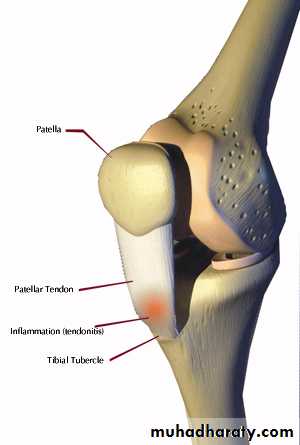

INJURIES

Rupture of the quadriceps apparatusOsgoodSchlatter's disease